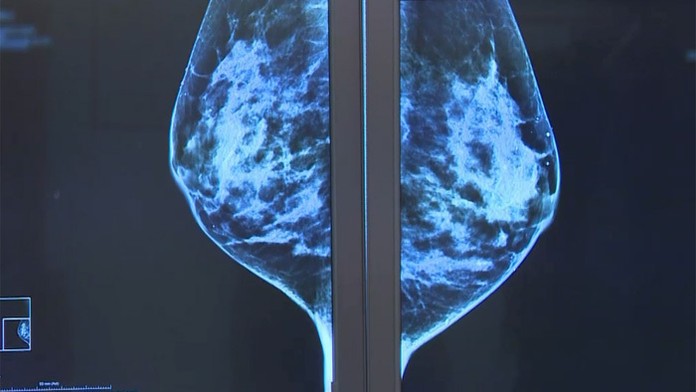

Karcinóm prsníka má stále viac a viac žien. Potvrdzuje to Svetová zdravotnícka organizácia, ale aj lekári na Slovensku.

Rakovina prsníka zostáva naďalej obrovským strašiakom žien. Lekári celosvetovo zaznamenávajú čoraz vyšší výskyt tohto zákerného ochorenia. Za jeho nárastom je starnutie populácie, ale aj zanedbaná prevencia. Vo svete ročne zomrie na rakovinu prsníka asi pol milióna žien.